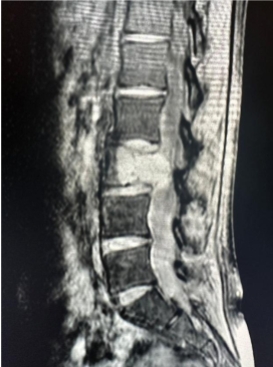

- X-rays (to assess spinal alignment and bending points)

- CT scans (for bony structures and abnormalities)

- MRI scans (to examine nerve and soft tissue damage)

- Blood tests (to check for neurological or autoimmune disorders such as Parkinson's disease)

Because DHS can mimic other diseases, an experienced specialist is necessary for an accurate diagnosis.